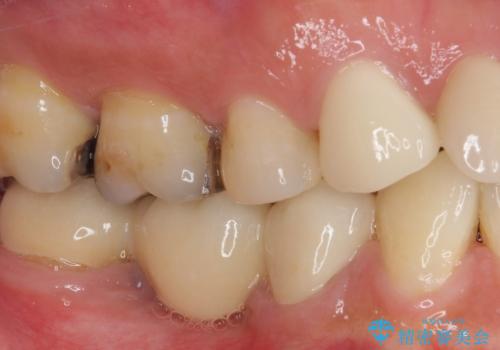

- 奥歯に痛みを感じるようになり、更にはその前の歯のセラミックが欠けてしまったとのことで来院された患者様です。

痛みがしばらく続いていたため、抜髄となる可能性を考慮しながら処置を行うこととしました。

処置後に痛みの状態を確認し、前歯のクラウンの再製作を同時に進めることとしました。

銀歯の下の虫歯はそれほど大きくなく、初回の処置以降、痛みを感じることはなくなりました。

セラミックインレー装着後も痛みが生じることはなく、神経の状態も正常な反応が認められました。